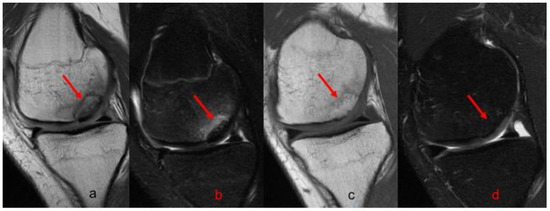

Postoperative radiographs and MRIs were used to classify and assess the healing of the treated lesion according to previously delineated criteria. (Figure 1, Figure 2 and Figure 3) A fluid interface between the OCD fragment and the condylar bone was considered a sign of incomplete consolidation. Then again, sclerosis or necrosis of the fragment were considered sign of non-consolidation [10,11].

In magnetic resonance images, the fragment was seen properly repositioned in all the knees. Some degree of postoperative MRI alteration was detected in 40.8% of the cases. Signs of incomplete consolidation were detected in 17.9%, the absence of consolidation was present in 7.6% of the patients, subchondral bone edema was present in 5.1% of the cases and cartilage fibrillation in 10.2% of the patients. Patients with any degree of consolidation disturbance in an MRI had inferior IKDC (p = 0.028) and Lysholm (p = 0.019) scores at the last follow-up. No statistical correlation was observed between any degree of MRI alteration and patient age whereas a weak correlation was observed with the area of the lesions (0.293).

Figure 2. MRI evolution of grade III OCD of 2.9 cm2 in the medial condyle of left knee fixed with two Herbert screws. (a) T1 preoperative sagittal view; (b) T2 preoperative sagittal view; (c) Table 1. One-year postoperative sagittal view; (d) T2 1 year postoperative sagittal view. In all images the red arrow indicates the lesion.